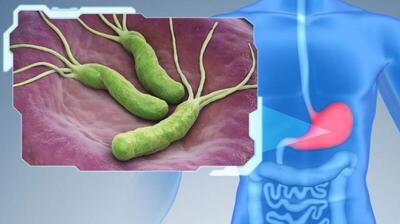

کرونا از طریق بلع منتقل میشود؟

گذر کرونا از معده و رسیدن آن به روده نکته مهمی است و مواد غذایی آلوده میتواند ویروس را از راه دهانی منتقل کند.